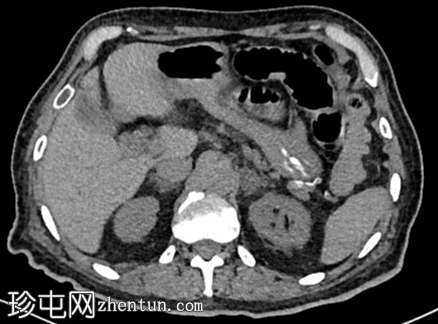

CT

9.png

这张4个月前的非增强CT图像显示,胰腺钩突周围及十二指肠第二段有轻微的饱满感。

这张4个月前的非增强CT图像显示,胰腺钩突及十二指肠第二段区域有轻微的饱满感。遗憾的是,这一发现被忽略了。

事后看来,这应该促使医生进行进一步评估。早期胰腺肿瘤在CT图像上可能表现为轻微的轮廓异常或局灶性饱满,很容易被忽略。当发现此类情况时,建议进行增强CT或MRI等专门的胰腺成像检查,因为早期发现可以显著影响治疗和预后。